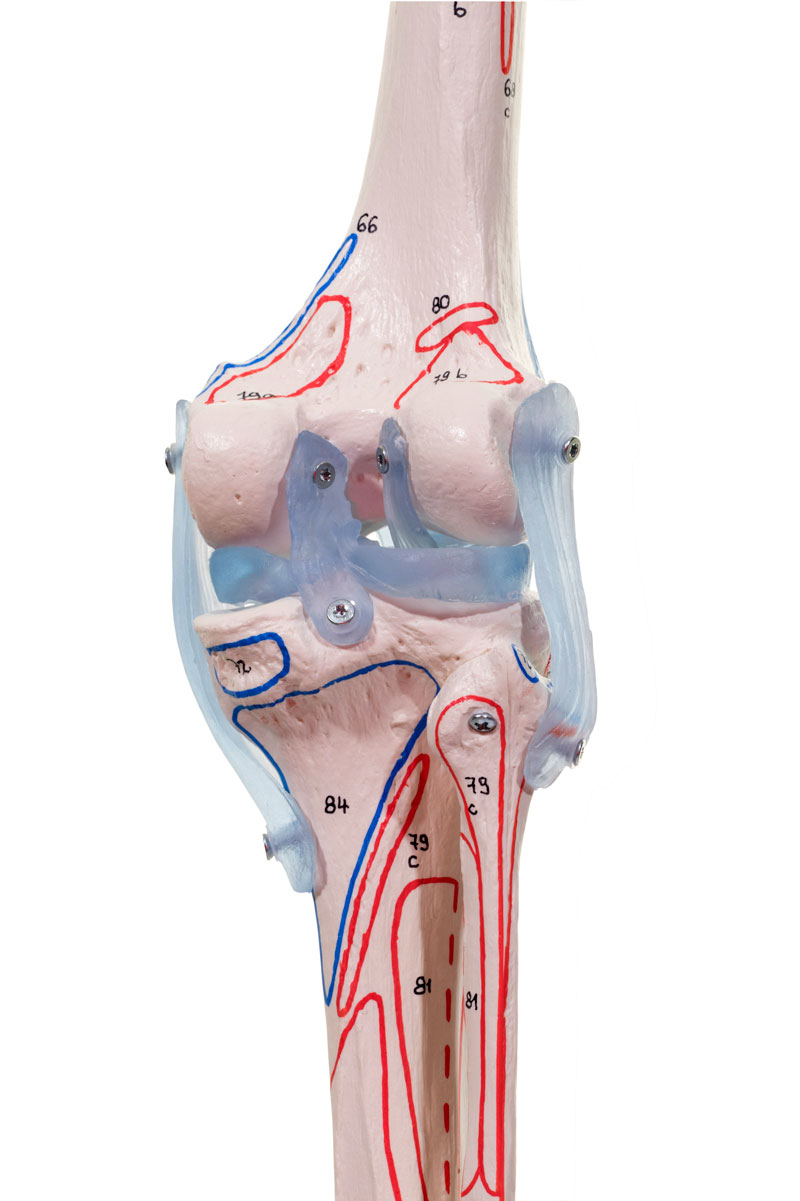

Ligaments

Avec ligaments